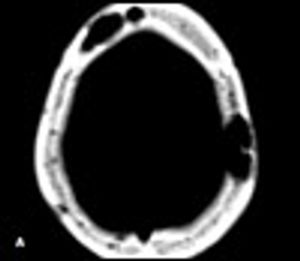

A39-year-old man with a history of AIDS and nonadherence to highly active antiretroviral therapy (HAART) presented with frontal headache and scalp pain of 2 weeks' duration. These symptoms were accompanied by nausea, weight loss, and generalized weakness. Physical examination revealed a small, tender scalp lump, 2 × 2 cm over the left parietal area. The findings from the rest of the examination were unremarkable.